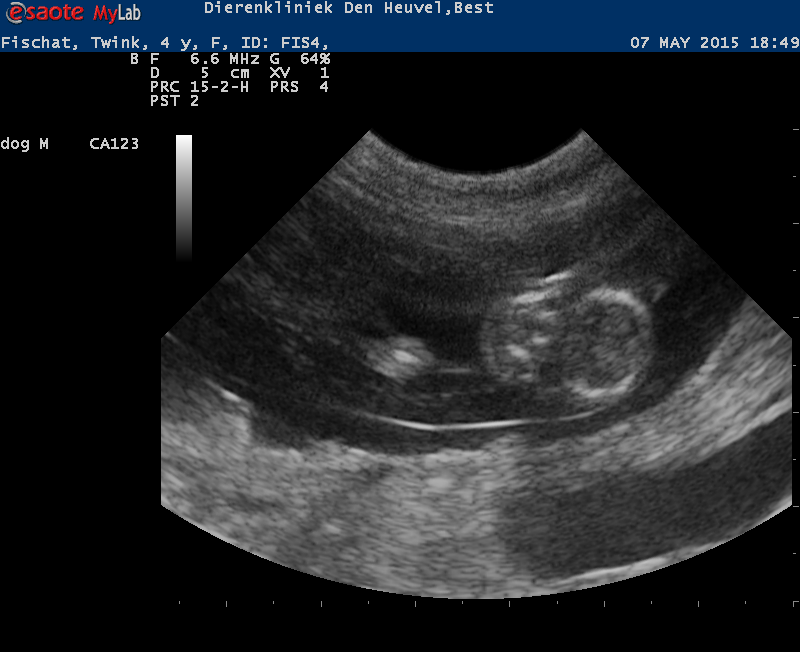

Wat een verdrietige tijdperk was, was er toch een klein lichtpuntje! Op de echo was te zien dat Bridget drachtig is en eind juli 2025 mogen we na 3 jaar eindelijk weer eens een nestje verwachten. Zo zie je maar weer dat het leven heel wisselvallig kan zijn en leven en dood zit heel dicht bij elkaar. Wij zijn dan ook reuze benieuwd naar de pups en nieuw leven!

Wij hadden al een tijdje een vermoeden, maar de echo heeft het bevestigd…. Wies is drachtig! Als alles goed gaat, verwachten wij in de eerste week van juni de puppies.